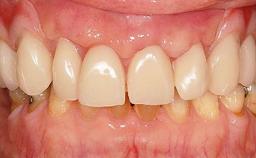

Surgical treatment of a 68-year-old female patient who experienced failure of her conventional bridge in the right maxilla. After removal of the compromised abutment teeth and a healing period of 6 weeks, a sinus floor elevation procedure using the lateral window technique and a composite graft to correct the insufficient bone height is carried out.

Two dental implants are placed in the same surgical session. The case concludes with the presentation of the final fixed dental prosthesis with a distal cantilever unit.

The 1-year follow-up radiographs demonstrate successful sinus floor elevation and stable bone crest levels around both implants, leading to a favorable long-term prognosis of the implant-supported prosthesis.